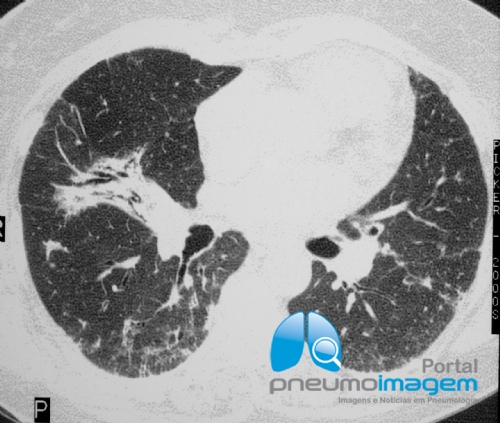

CASO CLÍNICO #51

Paciente do sexo feminino, 64 anos, com dispneia, tosse seca e deformidade articular nas mãos e punhos. Qual o provável diagnóstico? Deixe seus comentários abaixo.

A 64-year-old female patient with dyspnea, dry cough, and joint deformity in the hands and wrists. What is the probable diagnosis? Write your comment below.